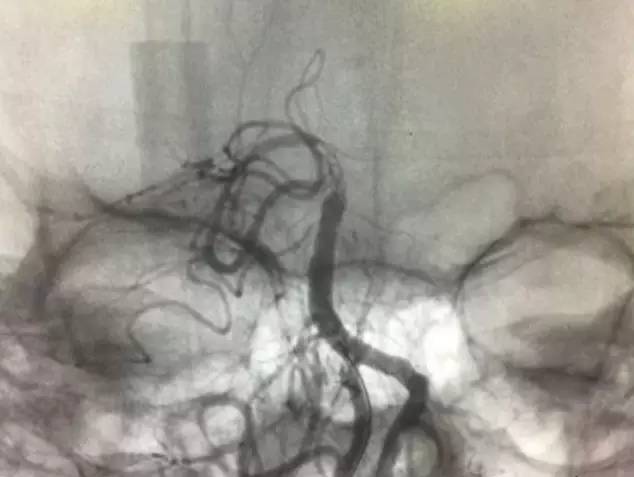

▼支架释放后,右大脑后及小脑上显影同时看到基底动脉的血栓,拉栓一次就再通。